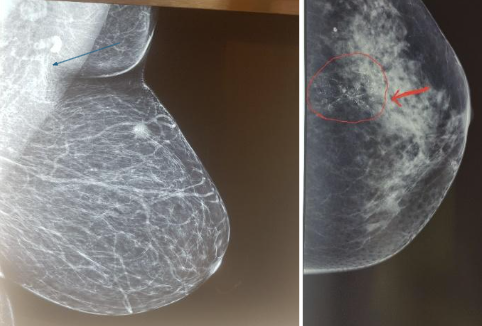

Mammography: A primary screening tool involving X-ray images of the breast tissue, recommended annually or biennially. Mammograms can detect tumors that may be too small to be felt.

Image 1

Biopsy: If a lump is found and its nature cannot be conclusively determined through imaging, or if it appears suspicious, a biopsy may be recommended. This involves the removal of a small tissue sample for examination to determine whether it is cancerous.